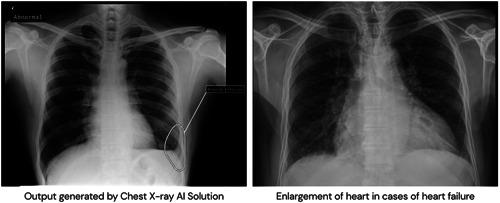

Typical signs of heart failure (HF), like increased cardiothoracic ratio (CTR) and pleural effusion, can be seen on X-ray. Artificial Intelligence (AI) can help in the early and quicker diagnosis of HF.

The study's goal was to demonstrate that the AI interpretation of chest X-rays can assist the clinician in diagnosing HF.

Patients older than 45 years were included in the study. The study analyzed 10 100 deidentified outpatient chest X-rays by AI algorithm. The AI-generated report was later verified by an independent radiologist. Patients with CTR > 0.5 and pleural effusion were marked as potential HF. Flagged patients underwent confirmatory tests, and those labeled as negative also underwent further investigations to rule out HF.

Out of 10 100, the AI algorithm detected 183 (1.8%) patients with increased CTR and pleural effusion on chest X-rays. One hundred and six out of 183 underwent diagnostic tests. Eighty-two (77%) out of 106 were diagnosed with HF according to current guidelines. From the remaining 9917 patients, 106 patients were randomly selected. Nine (8%) out of them were diagnosed with HF. The positive predictive value of AI for diagnosing HF is 77%, and the negative predictive value is 91%. More than half (54.9%) of newly diagnosed patients had HF with preserved ejection fraction.

HF is a risky condition with nonspecific symptoms that are difficult to diagnose, especially in the early stages. Using AI assistance for X-ray interpretation can be helpful for early diagnosis of HF especially HF with preserved ejection fraction.